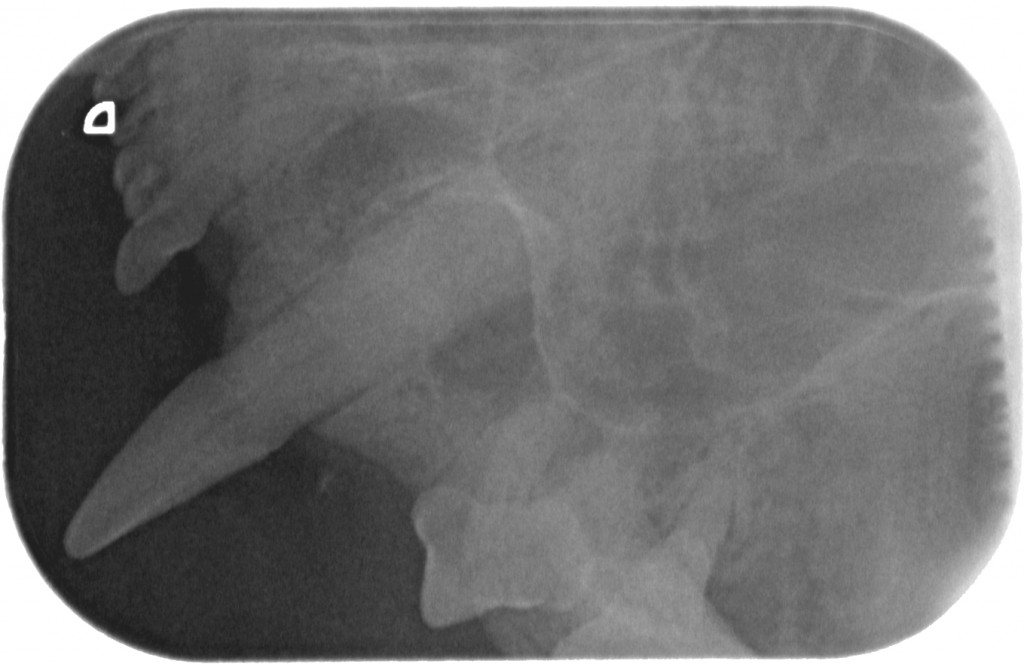

www.kattensliv.dk_Sygdomme hos katte fra P-T_Tænder_Mundproblemer_Shana-Mio_8

Rødt-tandkød-hos-kat-tænder-www.kattensliv.dk